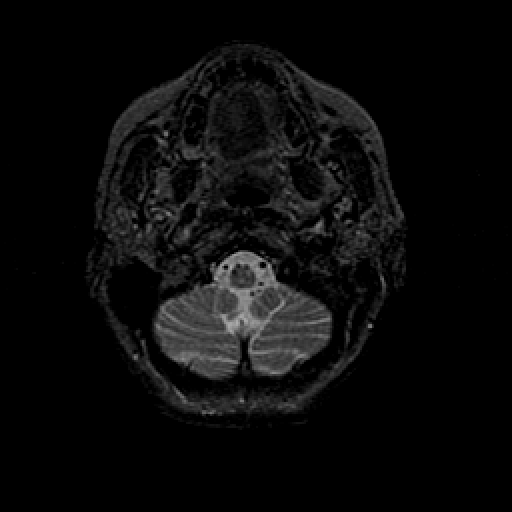

T2-weighted structural MR: Slice 6

Slice 6